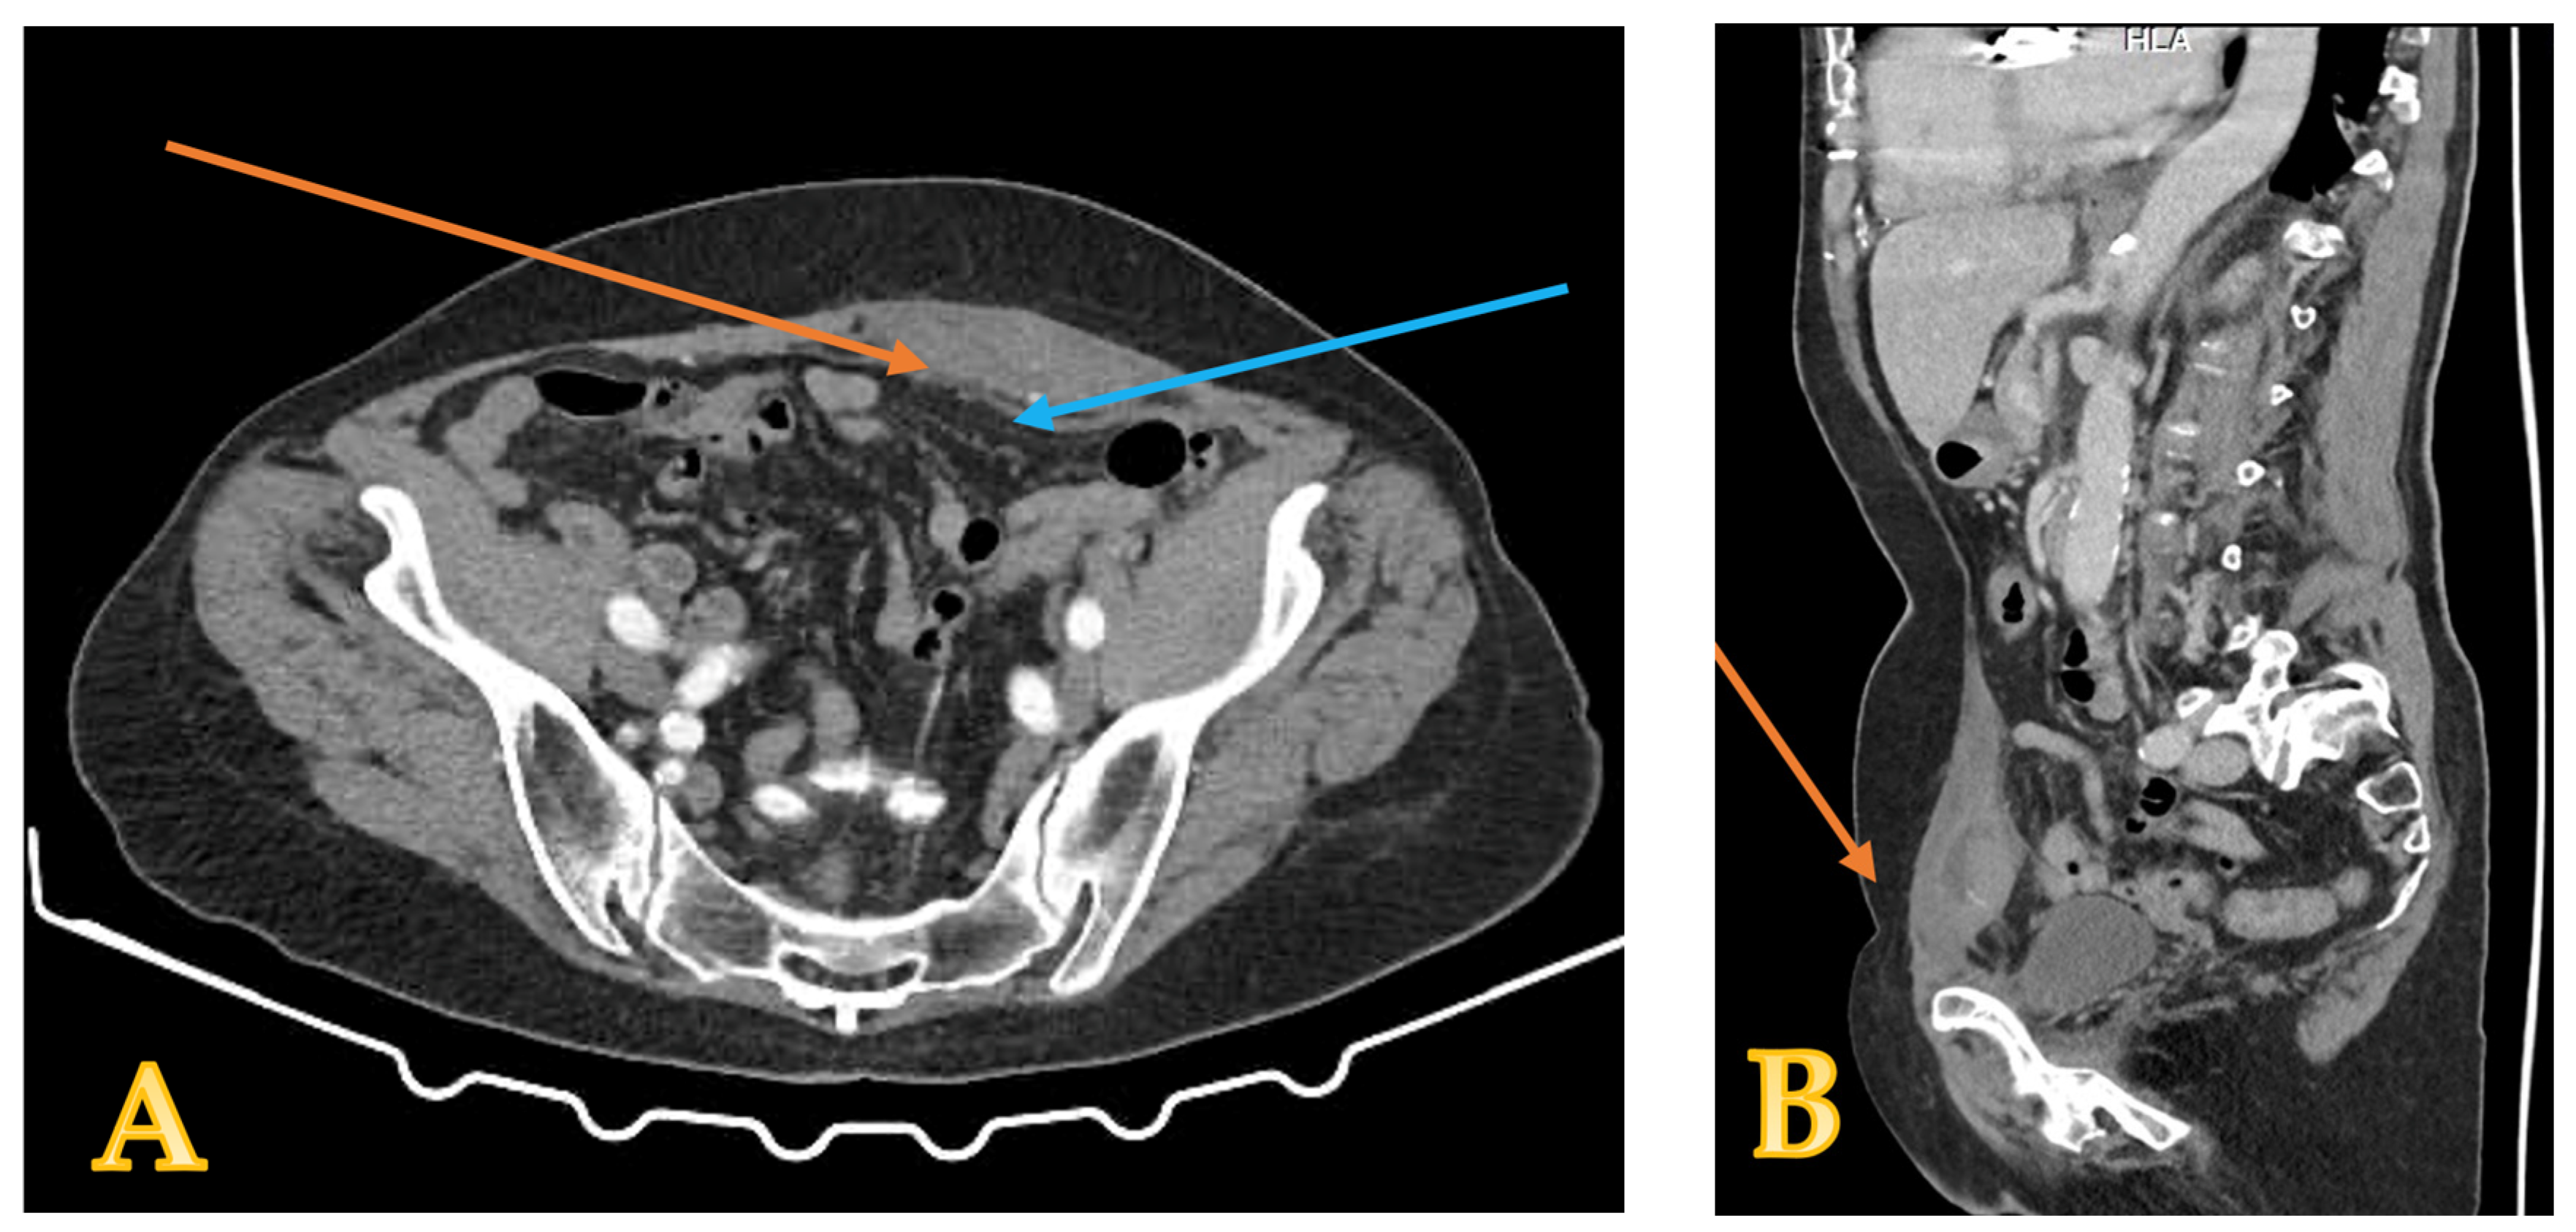

2. Case Presentation